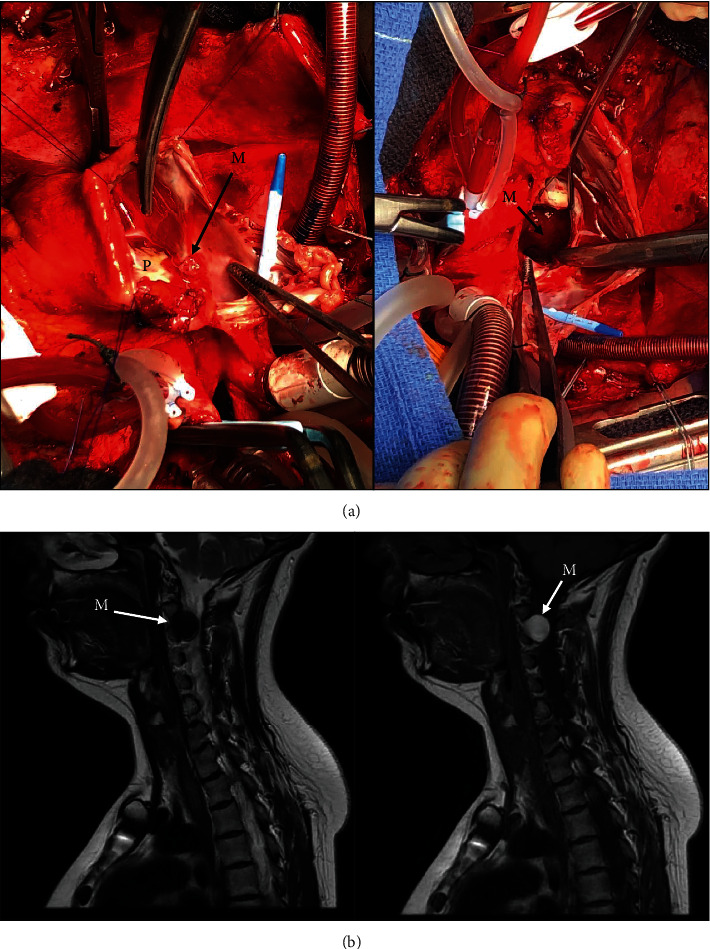

A 31-year-old female patient with a previous history of Carney complex and surgical resection for cardiac myxoma and bilateral adrenalectomy at 18 years old and 10 and 11 years old, respectively, was referred to our department with a diagnosis of recurrent biatrial myxomas incidentally discovered on echography. A magnetic resonance imaging (MRI) confirmed the diagnosis of a tumor protruding into the left ventricle, and the patient underwent a surgical resection of a large left atrial mass and a right-sided atrial small tumor. Diagnosis of bilateral atrial myxomas was confirmed by histologic studies. Postoperative outcome was uneventful, and the patient was discharged at the 7th postoperative day. Few months later, she reported trivial clinical symptoms suspecting a cervical radiculopathy. MRI confirmed the presence of a compressive cervical spinal cord tumoral mass at the C2-3 level leading to perform a surgical exeresis of the tumor. Histology showed a spinal melanotic schwannoma. This case highlights the risk of unexpected ubiquitary tumor locations and the importance of a rigorous transversal multidisciplinary follow-up to prevent severe complications in patients with Carney complex.